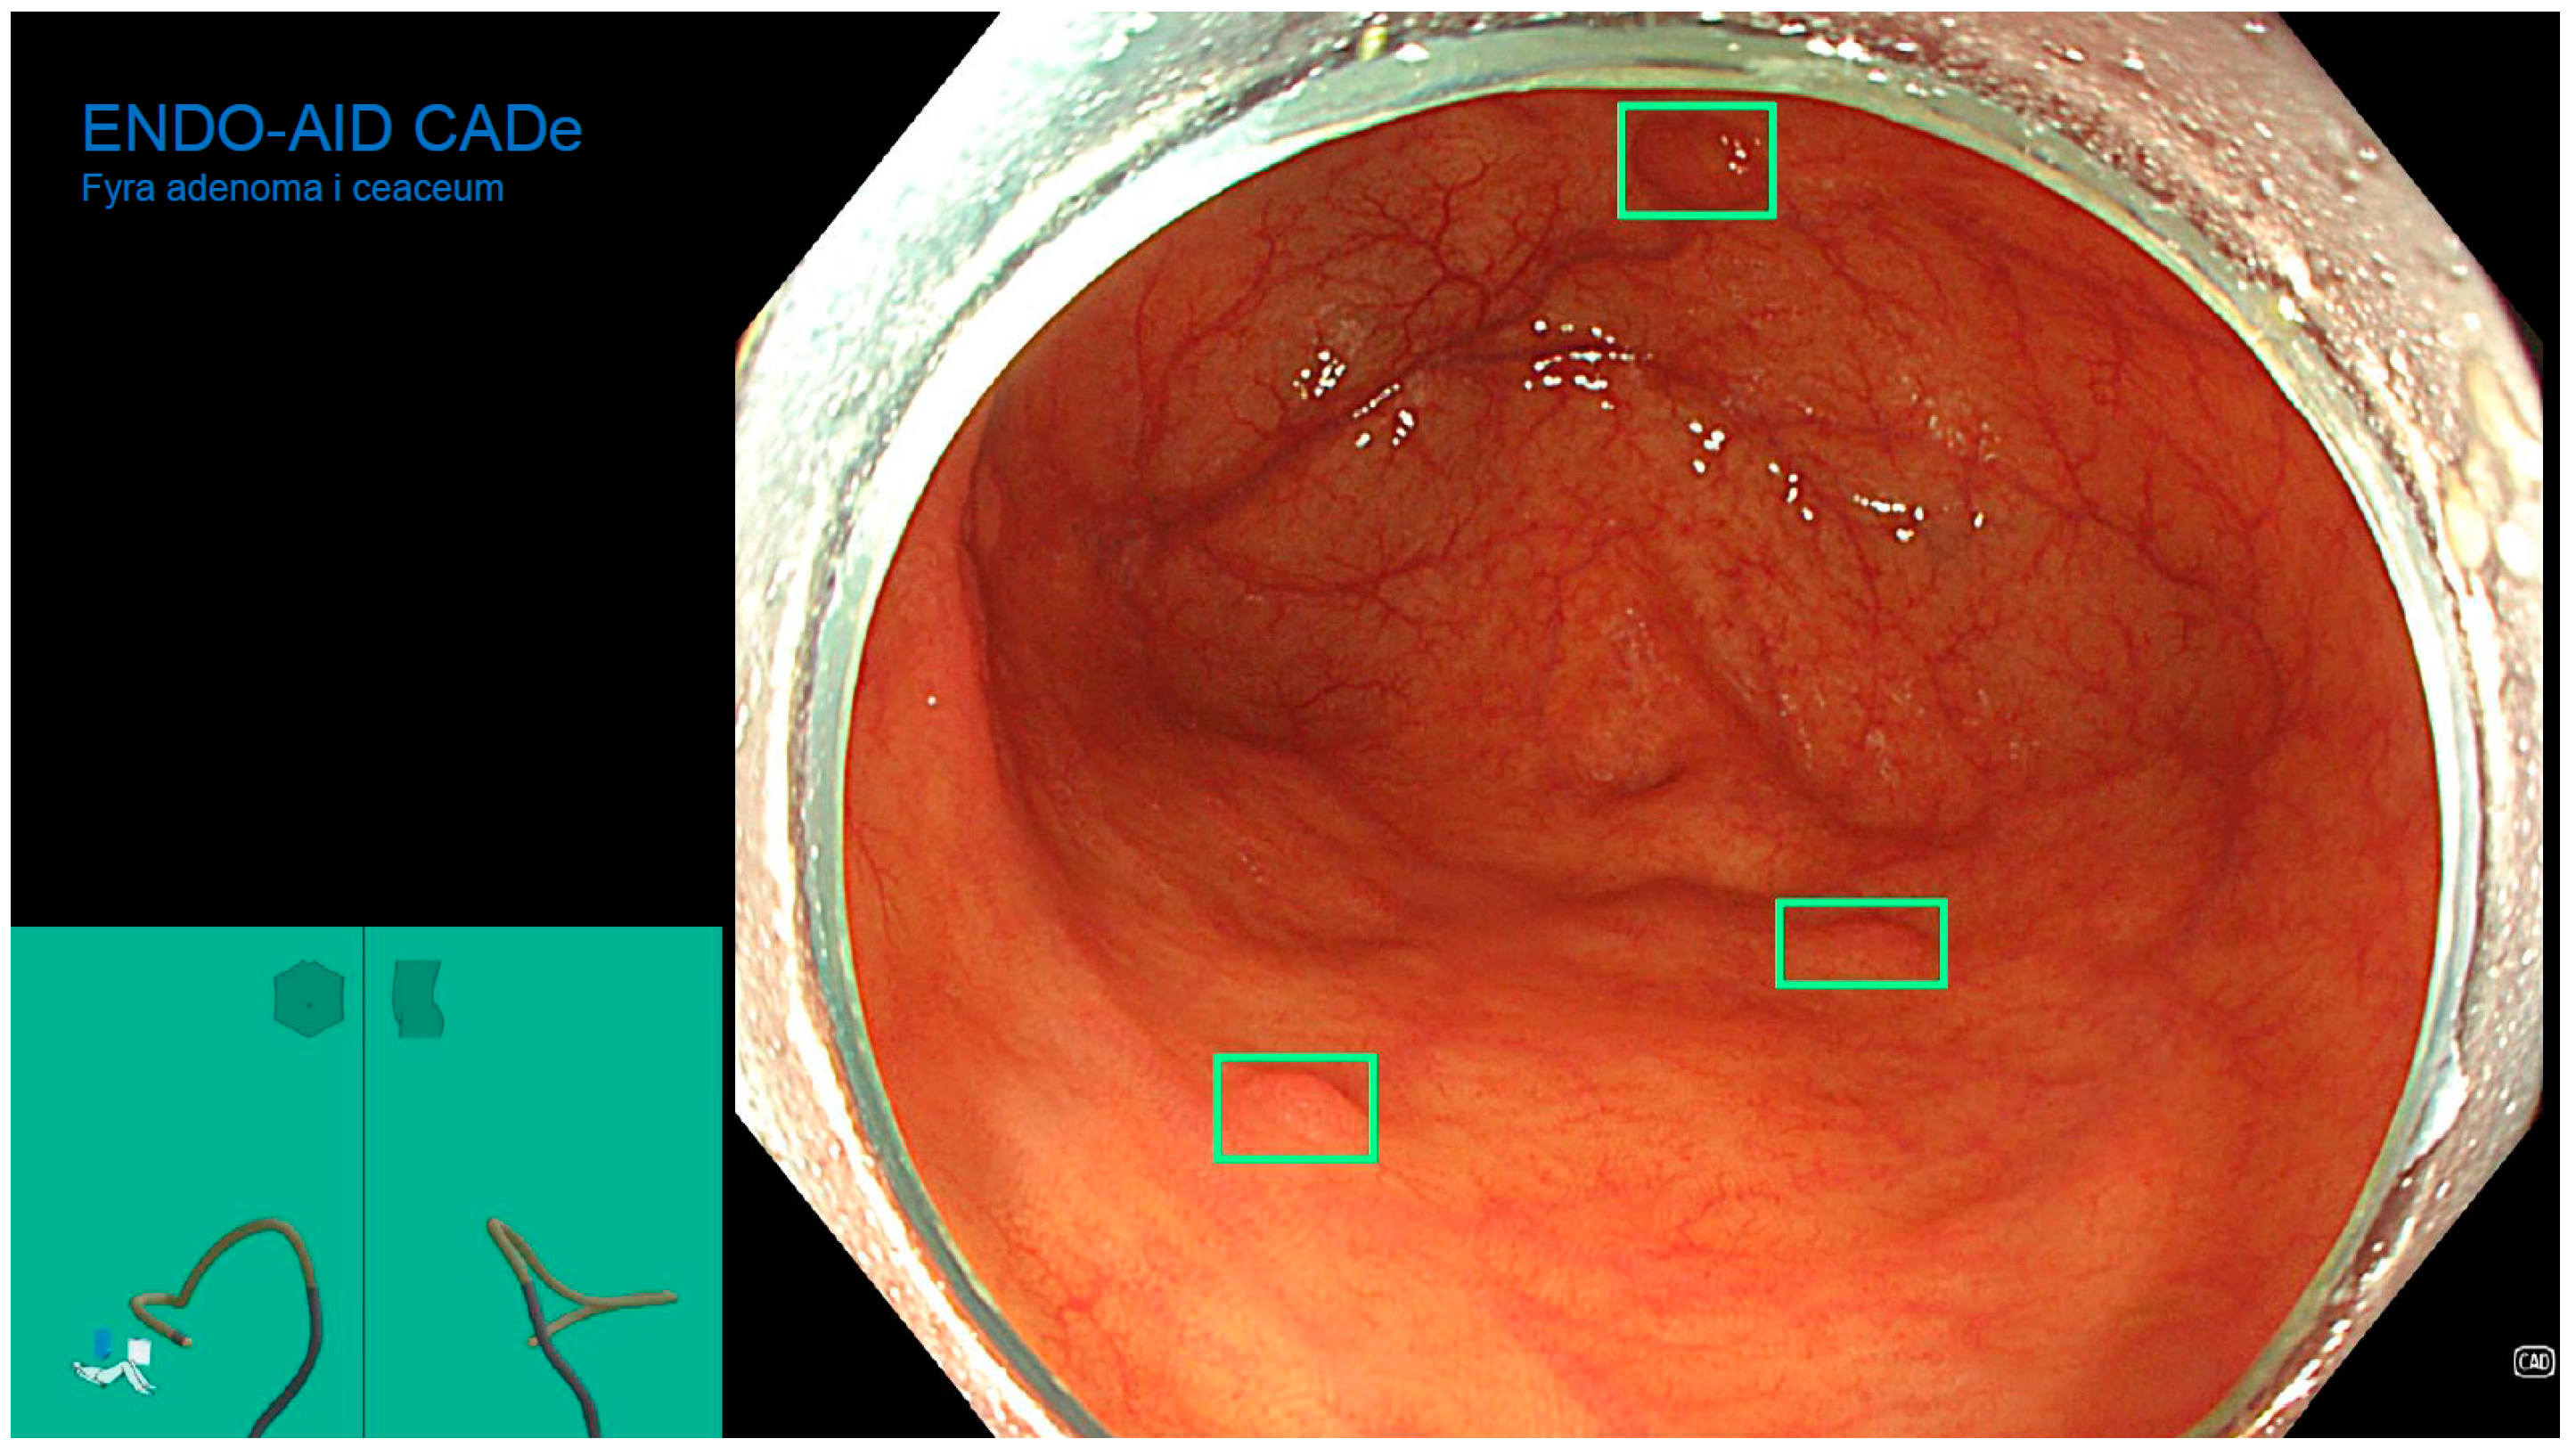

The Role of an Artificial Intelligence Method of Improving the Diagnosis of Neoplasms by Colonoscopy

2. Materials and Methods

2.4. Colonoscopy Procedure